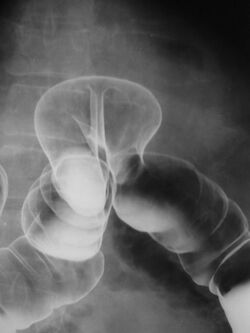

X-ray of colonic herniation

By far the most common hernias (up to 75% of all abdominal hernias) are inguinal hernias, which are further divided into the more common indirect inguinal hernia (2/3, depicted here), in which the inguinal canal is entered via a congenital weakness at its entrance (the internal inguinal ring), and the direct inguinal hernia type (1/3), where the hernia contents push through a weak spot in the back wall of the inguinal canal. An indirect inguinal hernia and a direct inguinal hernia can be distinguished by their positioning in relation to the inferior epigastric vessels. An indirect hernia is situated laterally to these vessels, whereas a direct hernia is positioned medially to them. Inguinal hernias are the most common type of hernia in both men and women. In some selected cases, they may require surgery.